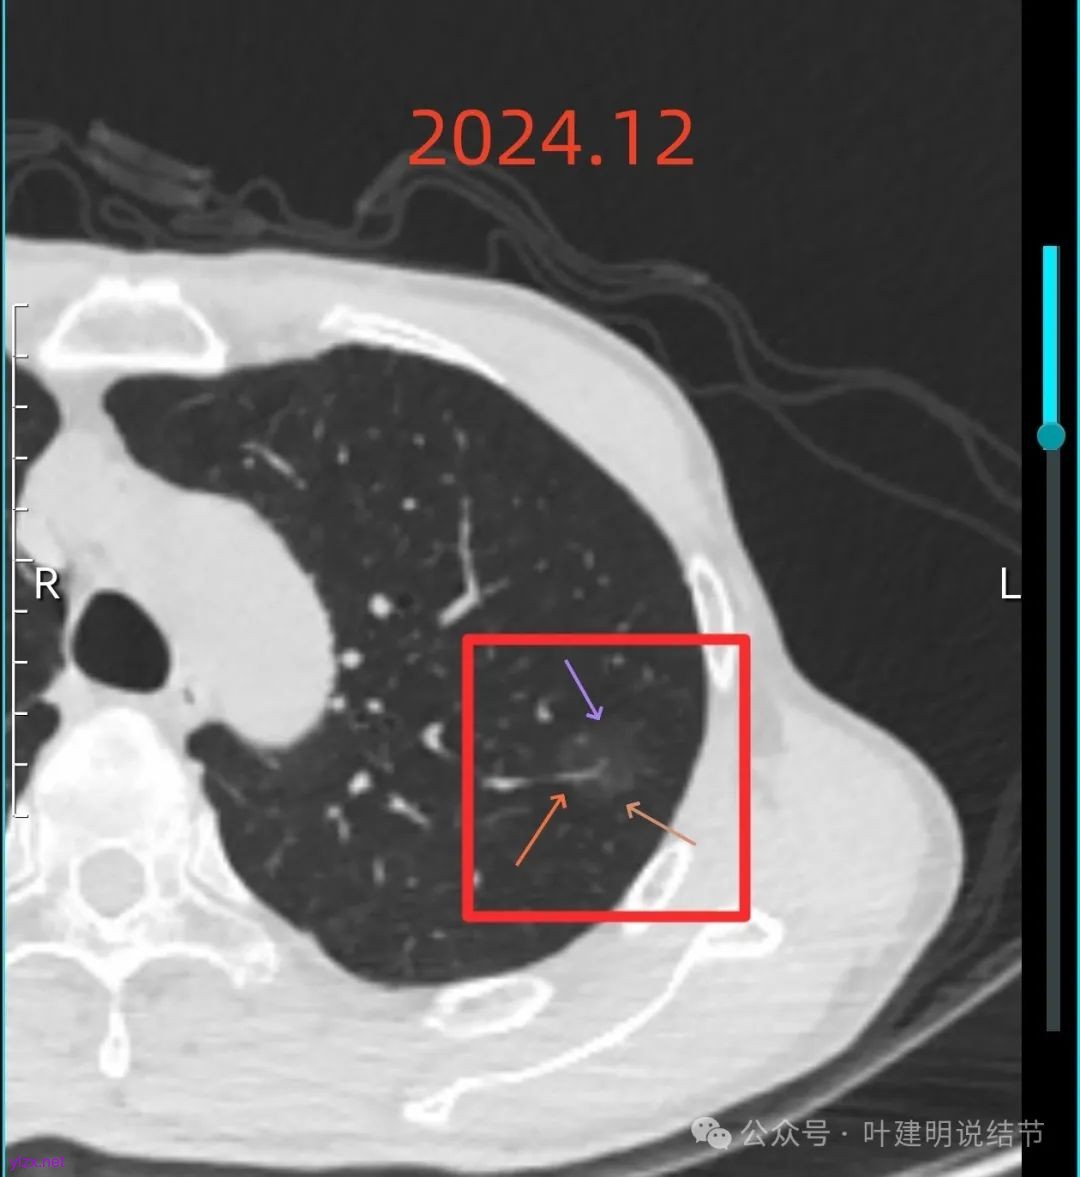

左上病灶血管进入了病灶且有异常增粗,边缘有淡的细毛刺的样子。

灶内血管明显,管壁略毛糙,有异常增粗,红色箭头处有点状高密度,边缘有毛刺征。

灶内出现了明显的实性成分,整体轮廓较清。

除了原血管进入外,另外角度也见到其他血管发出分支走向病灶,而且灶内密度不均,实性成分明显。

绿色的像是慢性炎,随访没有进展;红色的2022年12月开始是纯磨玻璃密度,但有小血管进入和整体轮廓较清,这种密度风险不高,但随访持续在的话,则要考虑肿瘤范畴,不典型增生或原位癌可能性大。再看2025年12月的,范围有所增大,磨玻璃部分密度仍很淡,但灶内出现实性成分,实性成分不太密实,稍显模糊。我觉得像微浸润性腺癌或原位癌伴肺泡塌陷可能性大。位置还好,病灶也不太小,若再增大进展切除范围更多些,我倾向单孔胸腔镜下局部楔形切了为妥。意见供参考!